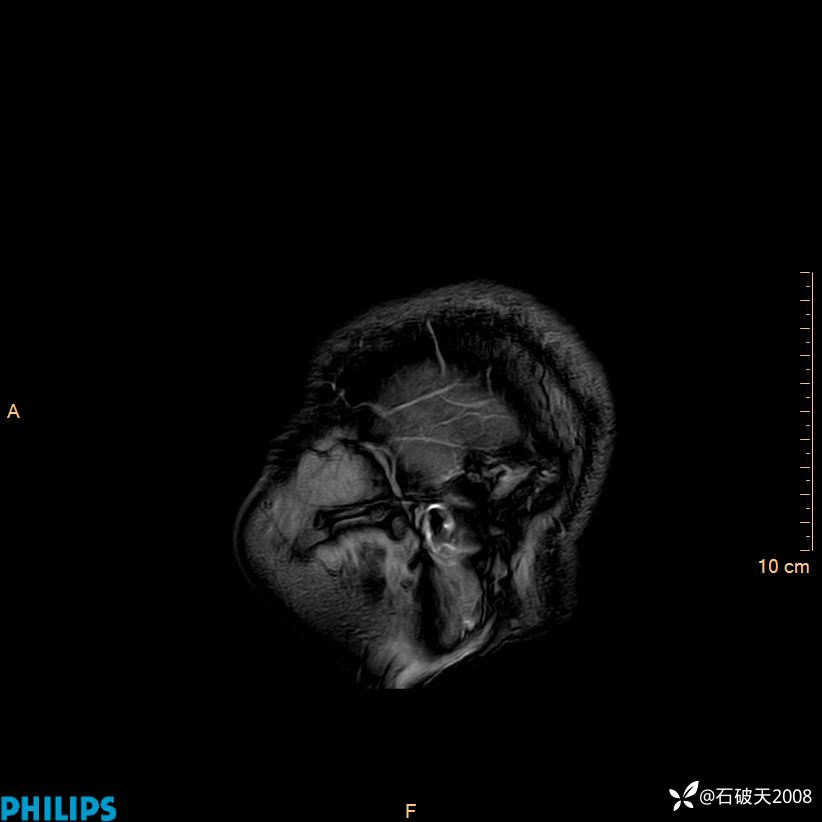

增强轴位